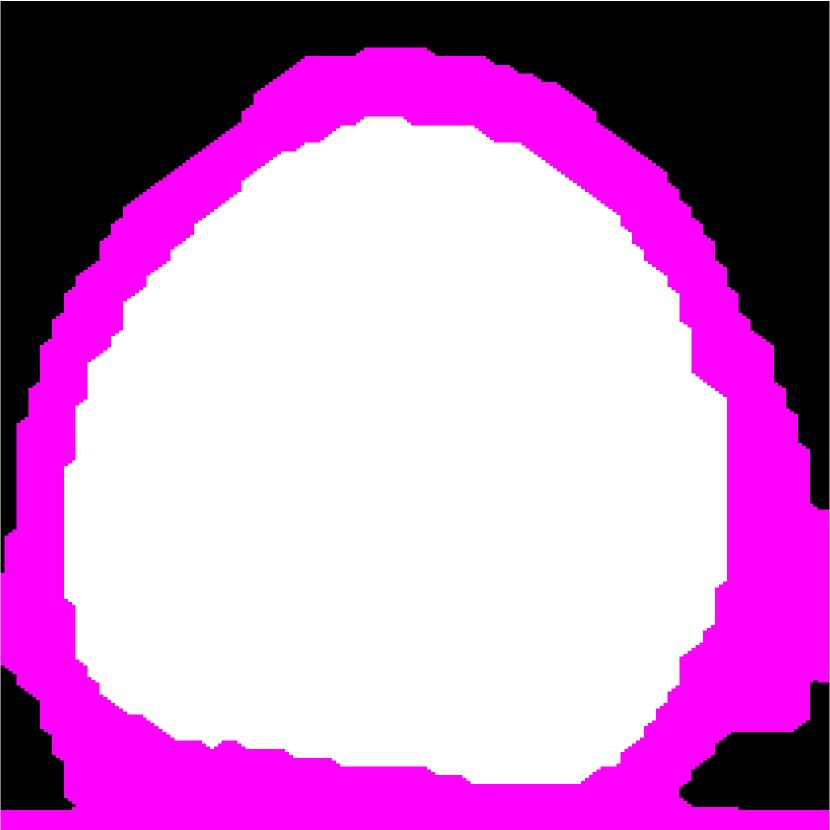

Figure 1: (a) Target HFU image. (b) Manual-segmentation result by an expert. LNP is white and fat region is pink. The vertical axis is depth. (c) The segmentation result obtained by K-means.

Figure 1(a) shows a representative HFU image of a human LN immersed in a phosphate-buffered saline (PBS) bath. Two different LN tissue types are visible: LNP (inside) and fat (surrounding). In order to perform QUS processing successfully, a 3D segmentation method is required to restrict QUS processing to LNP and to correct accurately for ultrasound attenuation [2]. Furthermore, accurate segmentation can provide detailed LNP shape information, which can be used to produce additional bio-markers of cancer.

Automatic LN segmentation in HFU images faces several challenges, such as speckle noise, low contrast between LNP and fat, implicit boundary and spatially varying intensity distributions caused by acoustic attenuation and focusing effects. Therefore, obtaining satisfactory results with intensity information alone is not possible. To illustrate this point, Figure 1(c) shows the result of a K-means analysis, which clusters voxels based on their intensities. Compared to manual segmentation result, some LNP voxels with high intensity are mislabeled as fat, and some LNP voxels with low intensity are mislabeled as PBS. Due to speckle noise and spatially varying intensity distributions in HFU images, other intensity-based segmentation methods such as region growing [7] would also yield unsatisfactory results.